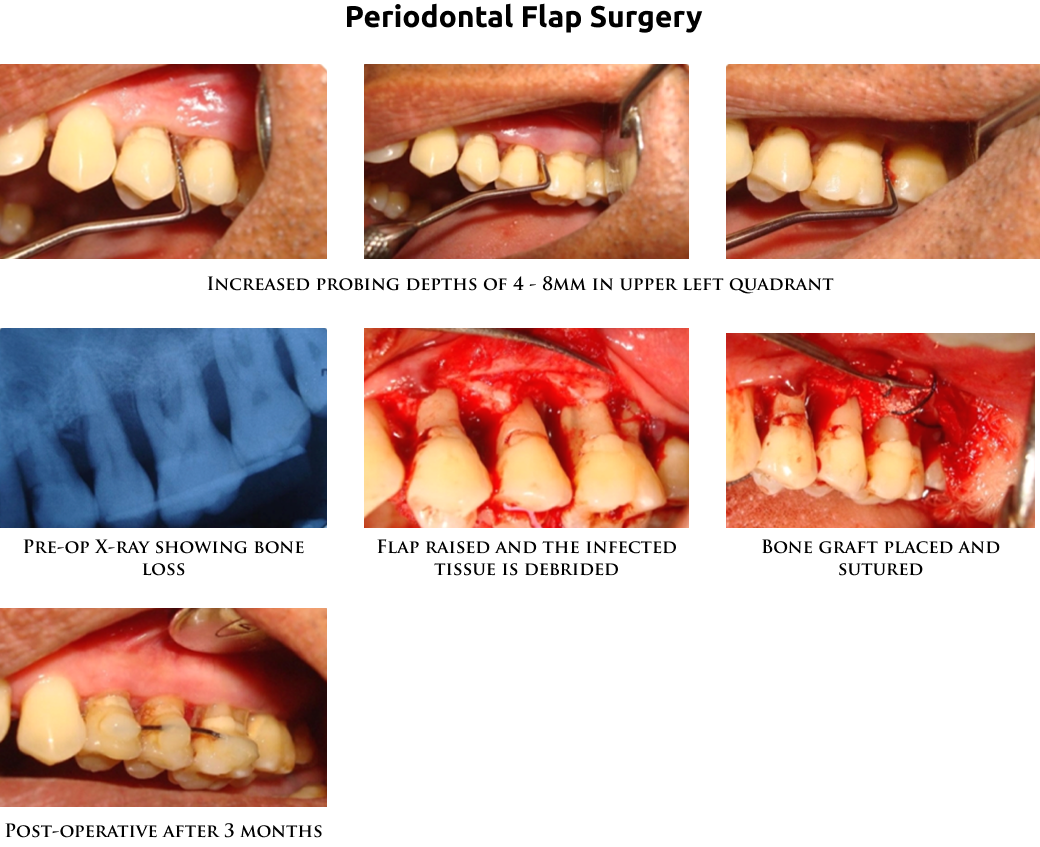

Periodontal flap surgery : It's done to reduce the pockets. The infection in the deeper portion of the gums are cleaned under local anesthesia. A cut is given, and the gums are raised above and hard deposits and infection is scraped and removed. Sometimes, in addition, bone grafts, gum grafts or guided tissue membranes may be needed to cover the root surface. The gums are sutured back. The loose gums are tightly attached to the bone after the healing period. Interdental aids need to be routinely used to keep the area clean.